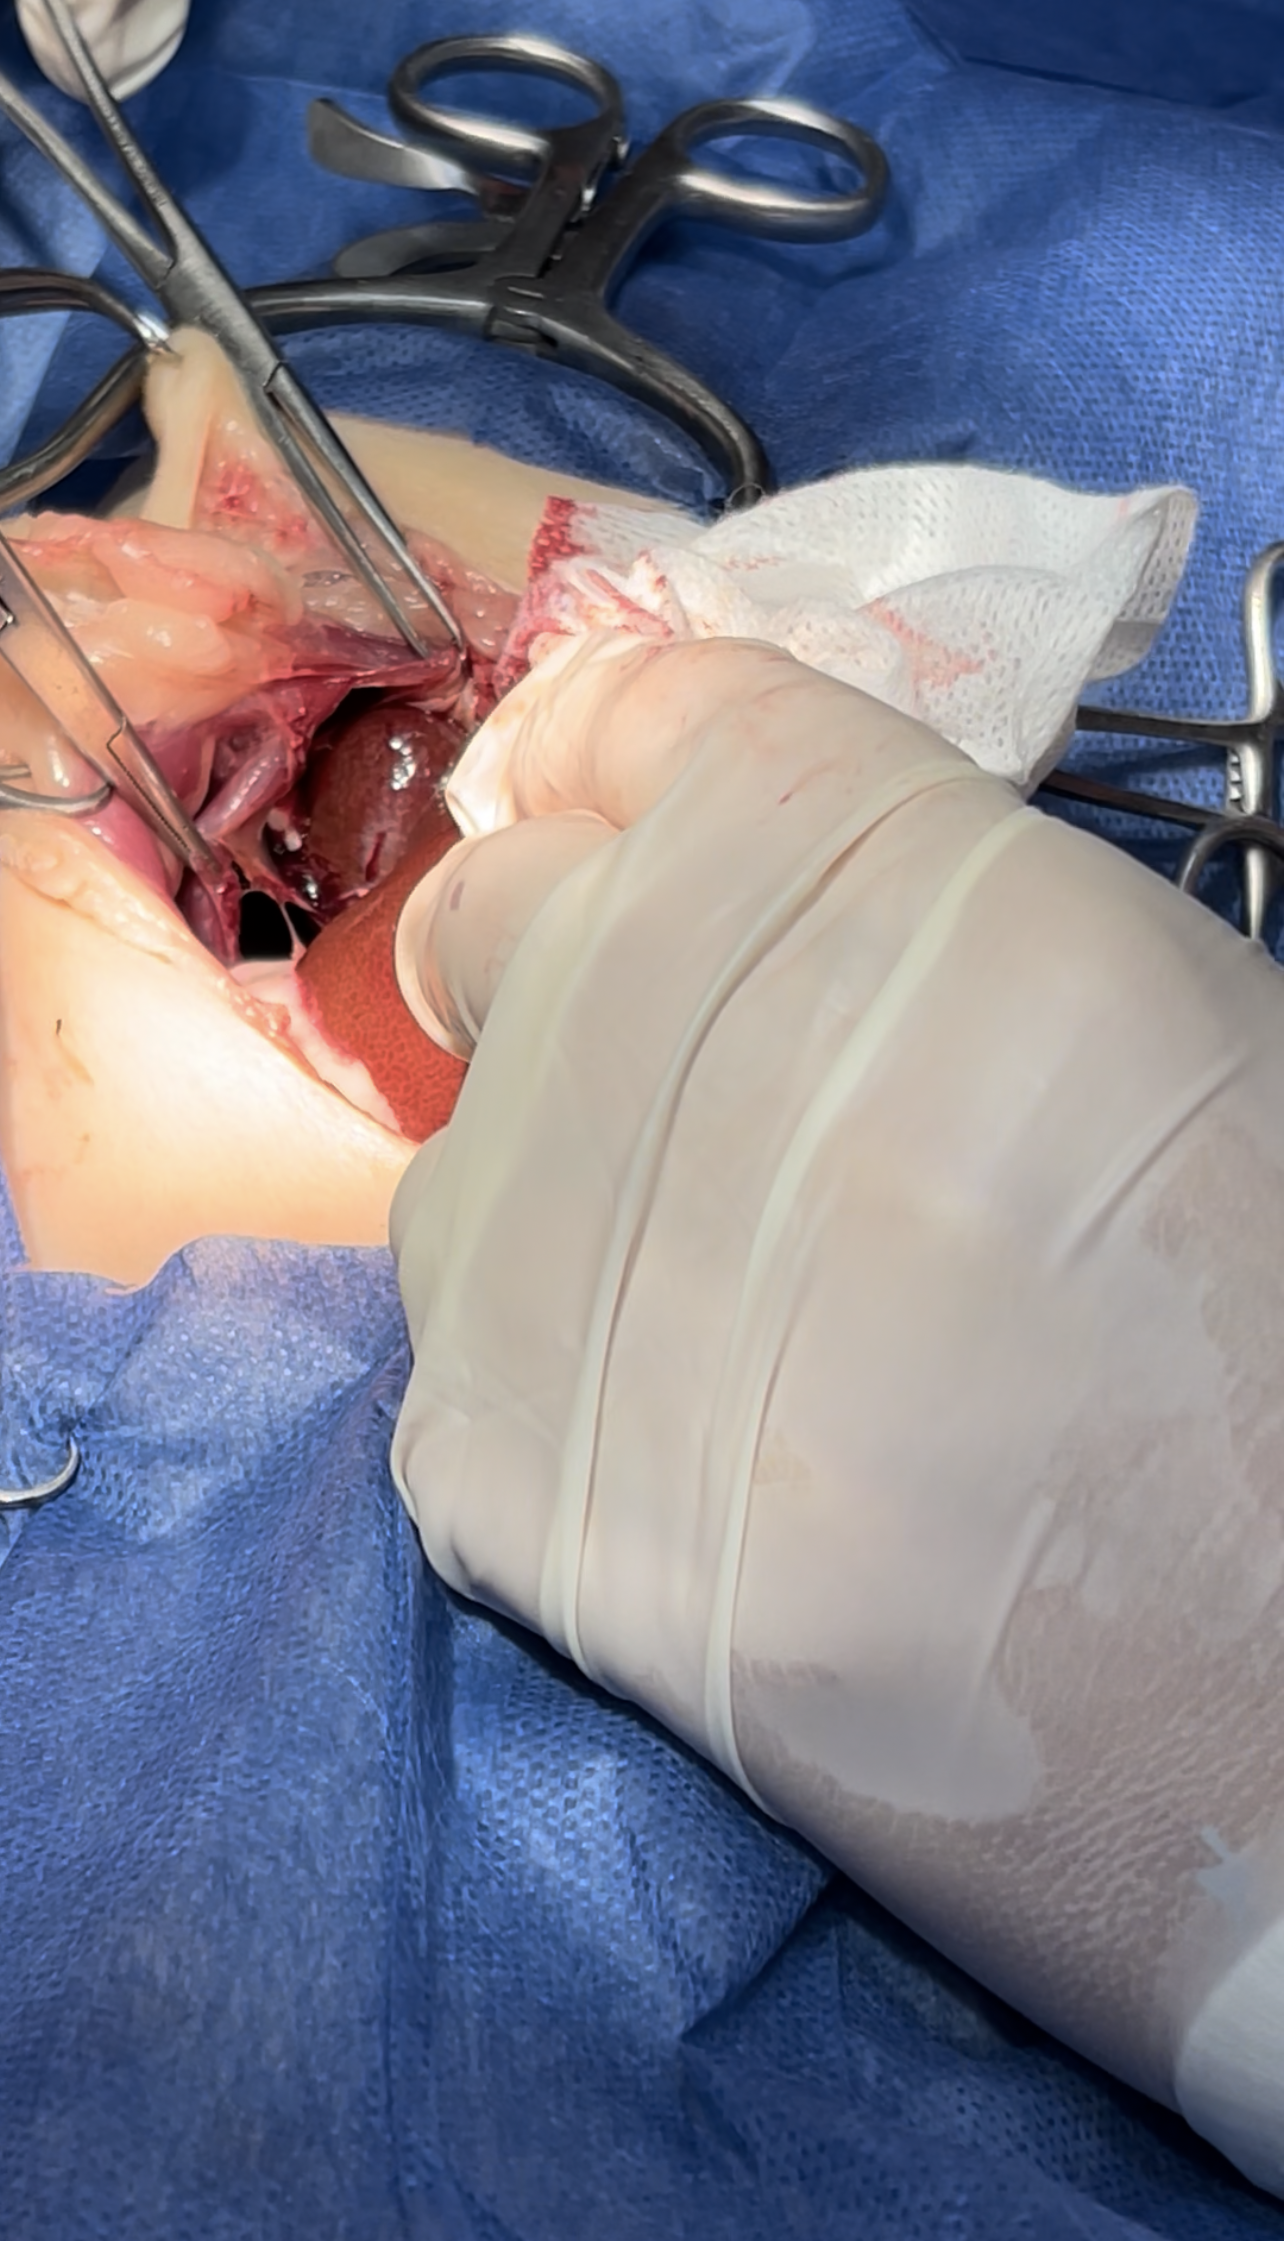

Dissection of the intraabdominal adhesive part of the live

Lacerations while dissection compressed with Gelfoam to minimize the parenchymal injury